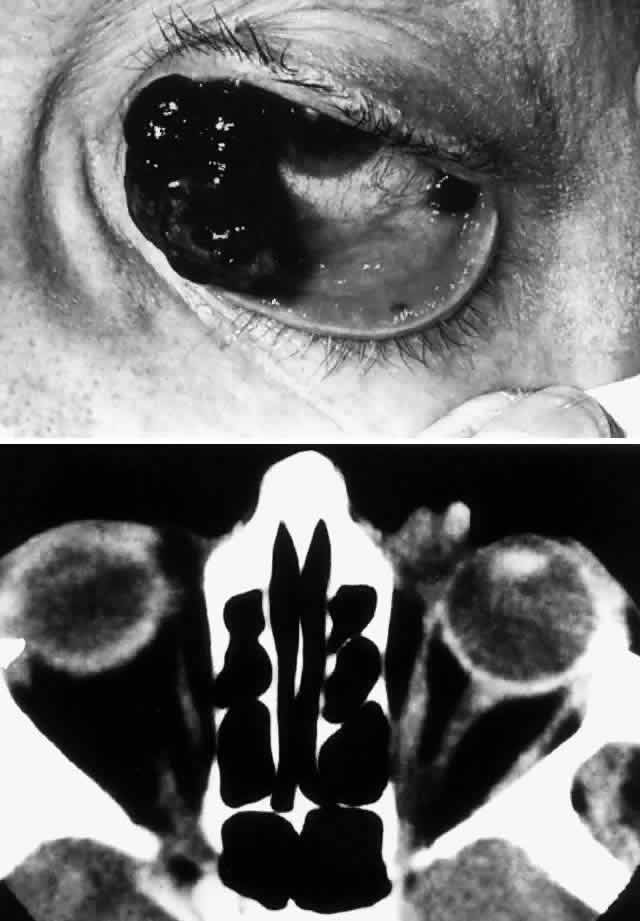

Fig. 1. A 59-year-old woman presented with a 6-month history of left infraorbital pain and dysesthesia. She was found to have maxillary antral squamous cell carcinoma and was treated with radiotherapy. Ten months after radiotherapy, severe left ocular and orbital pain associated with tearing and blurred vision developed. On examination, vision was 20/40 with a fixed, miotic pupil. A firm mass in the floor of the anterior orbit displaced the globe superiorly 5 mm and anteriorly 2 mm. Inferior chemosis, moderate restriction of upgaze, and an intraocular pressure of 30 mmHg (increasing to 40 mmHg on upgaze) were noted. Despite maxillectomy, orbital exenteration, and orbital radiotherapy, the patient had local recurrence and diffuse metastatic disease, and she died 10 months after orbital presentation.

Radiologic findings consist of either focal or widespread destruction of the sinuses, with invasion of the adjacent structures by a solid tumor mass (Fig. 2). The mass is usually large; however, sometimes it may be relatively small but may extend to adjacent structures, particularly in the case of adenoid cystic carcinoma (Fig. 3). The sinus and orbit may be the only structures involved, but there is frequently extension to the base of the skull.

Fig. 2. A 32-year-old woman presented with a 1-month history of sinus congestion and nasal obstruction unresponsive to antibiotics. In the 1 week preceding the initial exam, the right eye became progressively more prominent and showed tearing and redness. On examination, there was mild edema of the lower lid and dysesthesia in the distribution of cranial nerve V2, and the globe was displaced 6 mm laterally and 5 mm anteriorly. There was mild limitation of abduction, chemosis, and nasal choroidal folds. An axial CT scan revealed a diffuse, destructive soft tissue mass centered in the superior nasal passage and ethmoid sinuses extending into the right orbit in contiguity with the medial rectus (A). On enhanced coronal view, the tumor was noted to involve the right maxillary antrum and to extend superiorly into the anterior cranial fossa (B). Biopsy of the sinus (C) revealed an alveolar-type rhabdomyosarcoma (muscle stain, × 320).